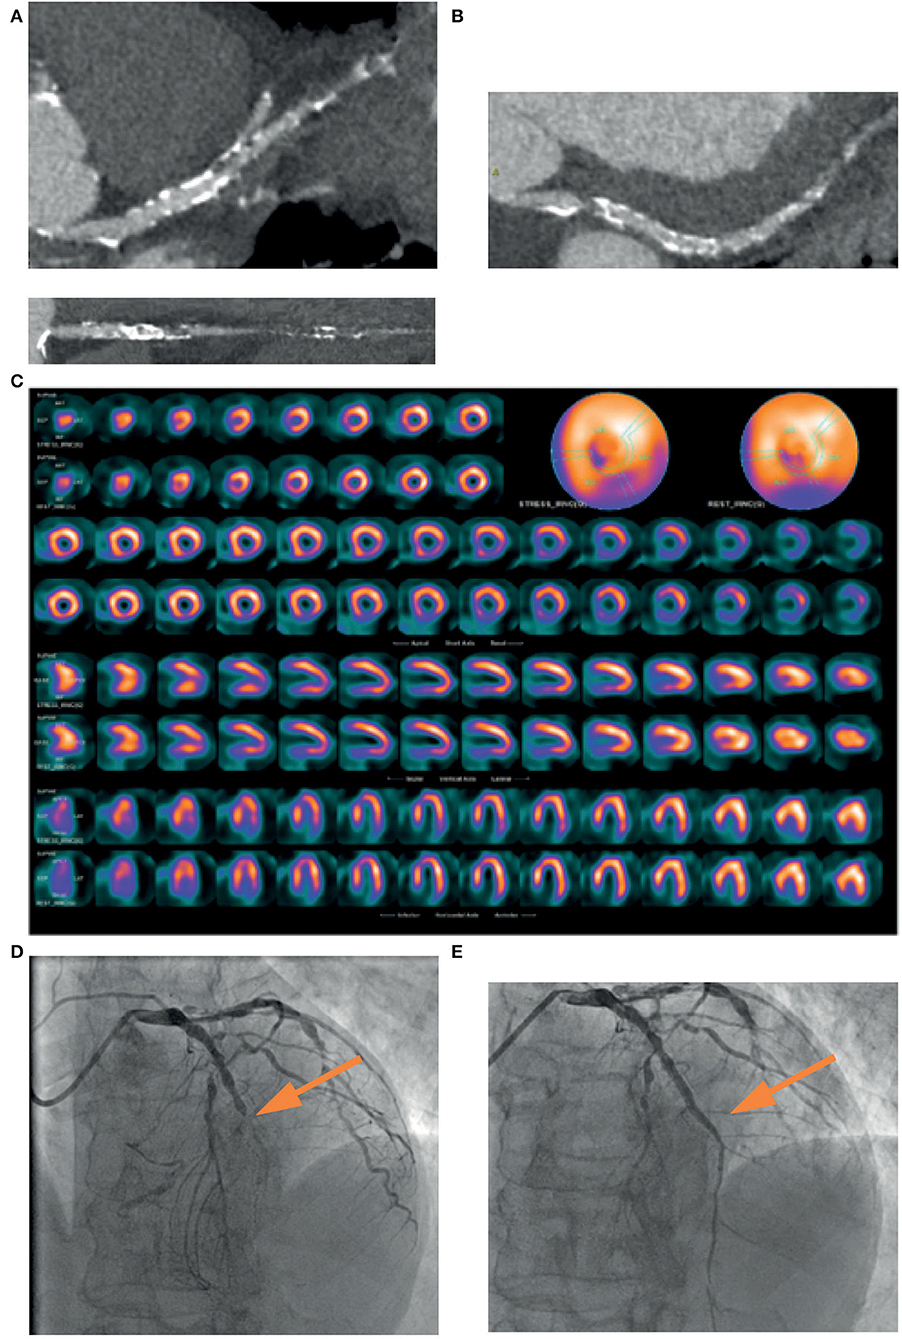

Figure 1. Example of the usefulness of multi-modality imaging in placing a correct indication for CTO percutaneous treatment. A 72-year-old patient performed a coronary computed tomography angiography (CCTA) (A) that showed severe three-vessel disease with occlusion (yellow arrow) of the left anterior descending (LAD) coronary artery. Coronary angiography (B) confirmed the presence of a calcified lesion occluding the LAD (yellow arrow) that was filled by means of collateral circulation. In consideration of the lack of symptoms and the unfavorable anatomy, it was decided not to proceed with a procedure without first assessing ischemia in the territory of the vessel. Cardiac stress magnetic resonance (C) showed inducible ischemia and myocardial viability in the mid-apical segment of the anterior wall and the interventricular septum (yellow arrow). Coronary angioplasty was then performed with implantation of a drug-eluting stent in the left main and LAD with an excellent result (D). Vessel patency without restenosis was confirmed by coronary CCTA at follow-up (E).